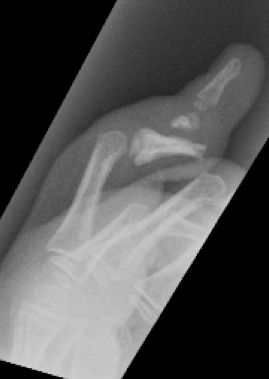

D3. Fracturas del cuello (subcondíleas)

Es una fractura extraarticular frecuente en la edad infantil y característica de lesiones por aplastamientos al cerrarse puertas de manera brusca al retirar la mano. Es más frecuente en la falange media del 2º o 5º dedo. El fragmento distal tiende a rotar a la extensión permaneciendo los ligamentos colaterales insertados en el fragmento distal.

Las fracturas no desplazadas del cuello de la falange se manejan con inmovilización con flexión de la articulación interfalángica durante 3-4 semanas. A pesar de ser fracturas alejadas de la fisis, en niños con potencial de crecimiento, menores de 8 años, se produce una buena remodelación de la fractura sin dejar secuelas cuando el desplazamiento es leve (Figura 23).

En el caso de fracturas muy desplazadas e inestables deben reducirse de manera cerrada y estabilizar con agujas cruzadas que se mantienen durante 3-4 semanas.

Se debe evitar atravesar la superficie articular con las agujas y utilizar agujas de diámetro adecuado para evitar secuelas, aunque en ocasiones es imposible sintetizarlas sin atravesar la articulación (Figura 24).